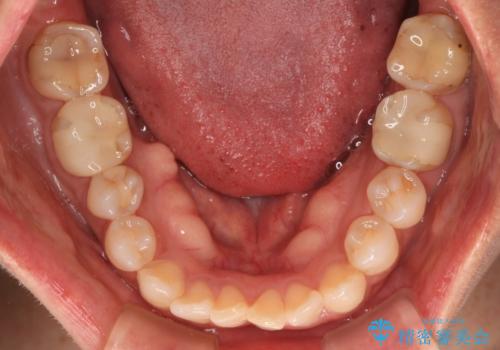

- 前歯のクロスバイトを気にして来院された患者様です。

上下ともに、前歯部を中心にやや叢生が認められる程度であったため、ワイヤーでもインビザラインでも、どちらでも対応可能な状態でした。

咬合力による臼歯離開は顎間ゴムで改善されましたが、それとは別に下顎小臼歯がマウスピースに追従せず、補正のためのゴムかけが必要となりました。

大変なゴムかけ作業を頑張っていただき、無事に治療を終えることができました。